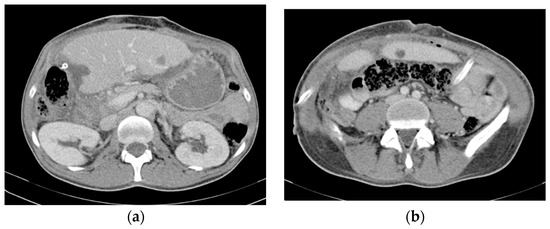

At this time, the treatment goal (set by a multidisciplinary team) was palliative because of the great disease burden in the liver, which was considered unresectable, and also because the ileal tumor did not show any acute complications (Hb = 9.3 g/L after administering 1 MER). Therefore, TKI therapy was initiated (Imatinib, 400 mg daily). The oncological follow-up at 2 months of TKI therapy showed a partial response according to the Choi criteria (the primary tumor measured 5.6 cm, and the liver metastases were stationary). Five months later, the primary tumor began to bleed significantly; therefore, emergency surgery involving a segmental ileal enterectomy with end-to-end anastomosis was performed. The preoperative MRI revealed stable disease according to the Choi criteria (Figure 2). The histological exam revealed an ileal gastrointestinal stromal tumor 6 cm in size, with a mitotic index greater than 5/50 HPF, with positive CD 117 and a Ki-67 Index of 25%, staging pT3 pN1 pM1hep (Figure 3).

Figure 2.

(a) MRI showing stable disease according to the Choi criteria of the primary tumor (arrowhead) (b) and of the liver metastases (arrows).